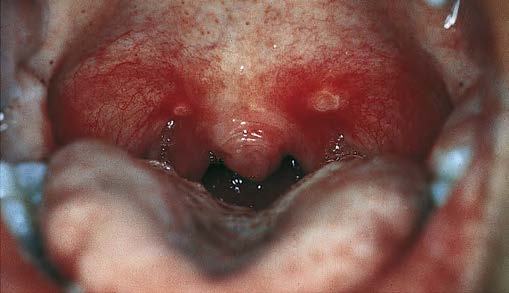

A five-year-old child presents with fever, irritability, and sore throat. Physical exam shows numerous small ulcers and vesicles inside his mouth. See picture:

Correct Answer A: Herpangina is a febrile disorder caused by numerous group A Coxsackie viruses and occasionally other enteroviruses. Infection produces oropharyngeal mucosal vesicular and ulcerative lesions.

Herpangina tends to occur in epidemics, most commonly in infants and children. It is characterized by sudden onset of fever with sore throat, headache, anorexia, and frequently, neck pain. Infants may vomit. Within 2 days after onset, up to 20 1- to 2-mm diameter grayish papules develop and become vesicles with erythematous areolae. They occur most frequently on the tonsillar pillars but also on the soft palate, tonsils, uvula, or tongue.

Diagnosis is based on symptoms and characteristic oral lesions. It is best confirmed by isolating the virus from the lesions or by demonstrating a rise in specific antibody titer, but such testing is not generally recommended. Treatment of herpangina is symptomatic.